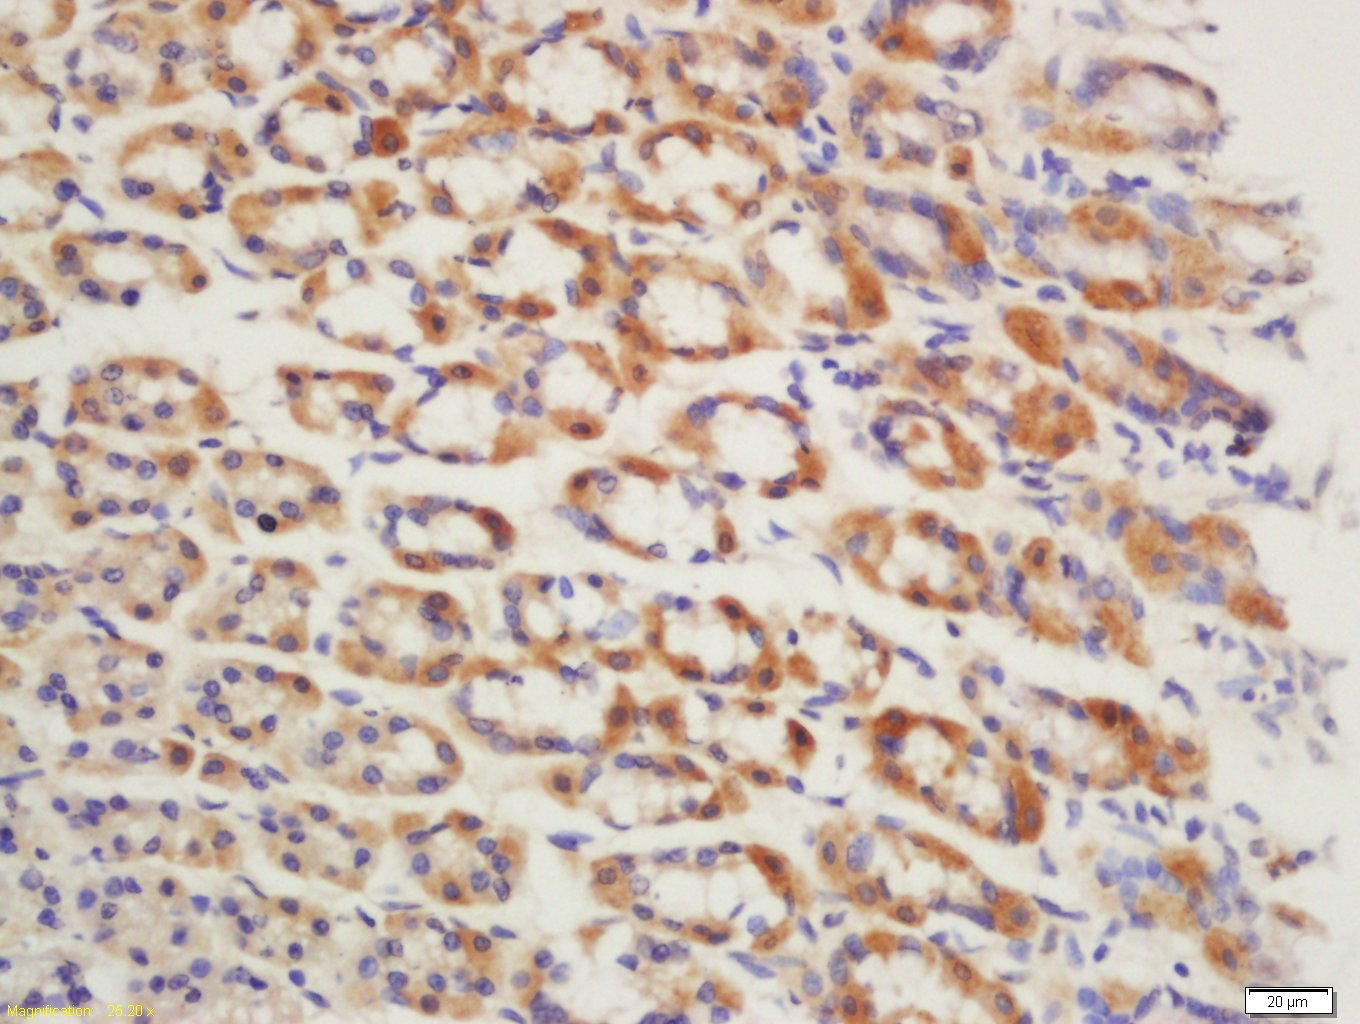

Tissue/cell: Mouse stomach tissue; 4% Paraformaldehyde-fixed and paraffin-embedded; Antigen retrieval: citrate buffer ( 0.01M, pH 6.0 ), Boiling bathing for 15min; Block endogenous peroxidase by 3% Hydrogen peroxide for 30min; Blocking buffer (normal goat serum,C-0005) at 37℃ for 20 min; Incubation: Anti-GPR15 Polyclonal Antibody, Unconjugated(bs-3699R) 1:200, overnight at 4°C, followed by conjugation to the secondary antibody(SP-0023) and DAB(C-0010) staining